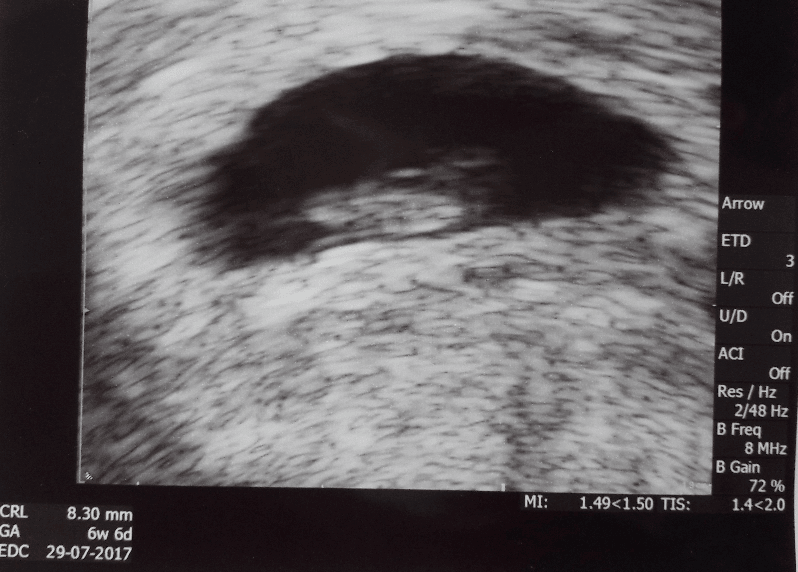

Zycze wam moje kochane tej samej foty

Bedzie corka prawdopodobnie